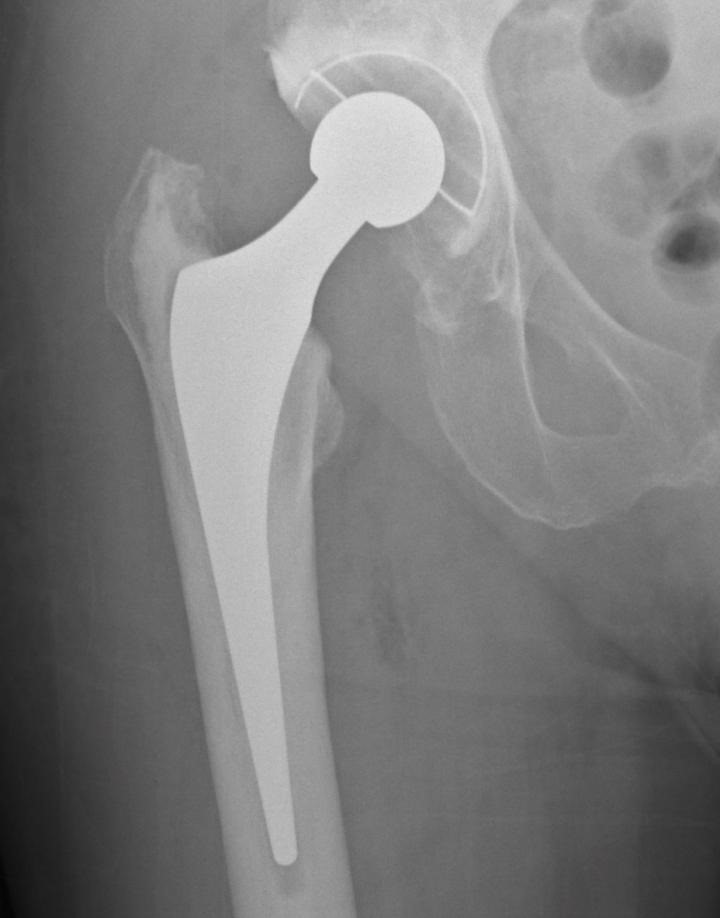

Radiografía de reemplazo de cadera

La fractura de maluc, una de les lesions més freqüents entre la població d'edat avançada, s'associa a un notable augment de la mortalitat i a una deterioració funcional significativa en els mesos posteriors a l'accident. Diversos estudis clínics i especialistes en traumatologia adverteixen que, encara que la lesió no sol ser la causa directa de la defunció, pot desencadenar un procés de declivi físic difícil de revertir en pacients vulnerables.